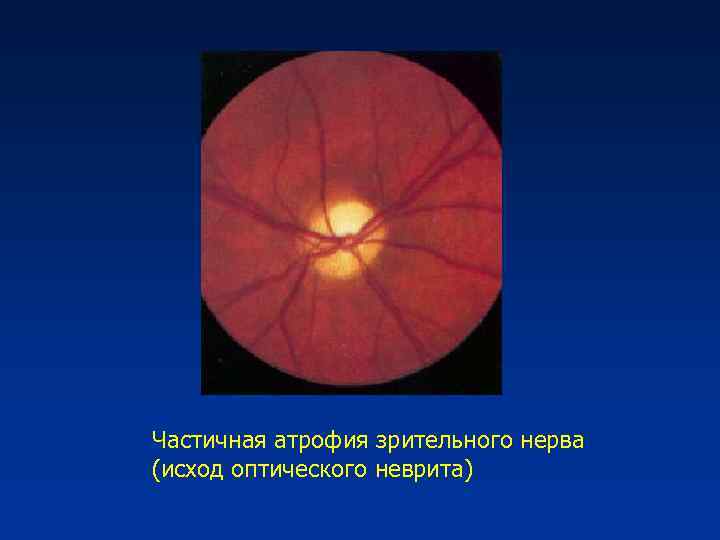

Атрофия зрительного нерва Лебера: Симптомы и лечение